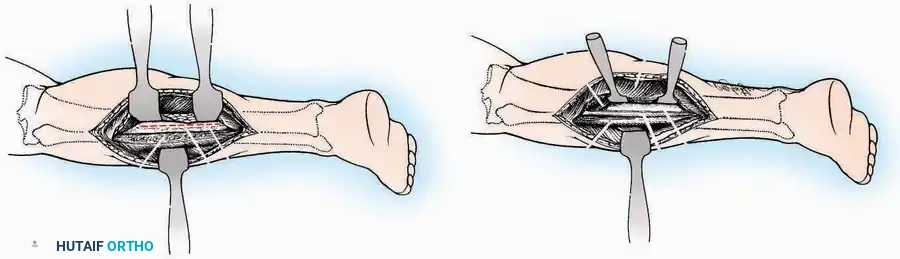

SURGICAL APPROACHES TO THE CALCANEUS

Approaches to the calcaneus are dictated by the pathology—trauma (intra-articular fractures) versus tumor/infection. Positioning is critical; while the prone position offers excellent bilateral access, the lateral decubitus or modified supine positions are more frequently utilized for unilateral trauma.

Lateral Approach (Extensile Lateral)

This is the workhorse approach for open reduction and internal fixation (ORIF) of displaced intra-articular calcaneal fractures.

Indications: ORIF of calcaneus fractures, lateral wall exostectomy, subtalar arthrodesis.

Positioning: Lateral decubitus with the operative leg up, or supine with a large bump under the ipsilateral hip to internally rotate the leg.

Surgical Technique:

* Incision: Begin the incision on the lateral margin of the Achilles tendon near its insertion. Extend it distally to a point 4 cm inferior and 2.5 cm anterior to the lateral malleolus. (For trauma, a classic L-shaped extensile incision is often used, dropping straight down anterior to the Achilles, then curving gently toward the base of the 5th metatarsal).

* Superficial Dissection: Divide the superficial and deep fasciae. It is imperative to create a "full-thickness" flap containing skin, subcutaneous fat, and periosteum to prevent flap necrosis.

* Nerve Protection: The sural nerve crosses the proximal and distal limbs of this approach. It must be identified and protected within the anterior flap.

* Deep Dissection: Isolate the peroneal tendons (longus and brevis). Incise and elevate the periosteum below the tendons to expose the lateral wall of the calcaneus.

* Tendon Management: If severe deformity or infection is present, the peroneal tendons may be divided via Z-plasty and repaired at the conclusion of the case, though this is rarely necessary in modern fracture care.